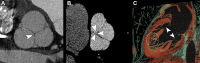

CT systems equipped with photon-counting detectors (PCDs), referred to as photon-counting CT (PCCT), are beginning to change imaging in several subspecialties, such as cardiac, vascular, thoracic, and musculoskeletal radiology. Evidence has been building in the literature underpinning the many advantages of PCCT for different clinical applications. These benefits derive from the distinct features of PCDs, which are made of semiconductor materials capable of converting photons directly into electric signal. PCCT advancements include, among the most important, improved spatial resolution, noise reduction, and spectral properties. PCCT spatial resolution on the order of 0.25 mm allows for the improved visualization of small structures (eg, small vessels, arterial walls, distal bronchi, and bone trabeculations) and their pathologies, as well as the identification of previously undetectable anomalies. In addition, blooming artifacts from calcifications, stents, and other dense structures are reduced. The benefits of the spectral capabilities of PCCT are broad and include reducing radiation and contrast material dose for patients. In addition, multiple types of information can be extracted from a single data set (ie, multiparametric imaging), including quantitative data often regarded as surrogates of functional information (eg, lung perfusion). PCCT also allows for a novel type of CT imaging, K-edge imaging. This technique, combined with new contrast materials specifically designed for this modality, opens the door to new applications for imaging in the future.